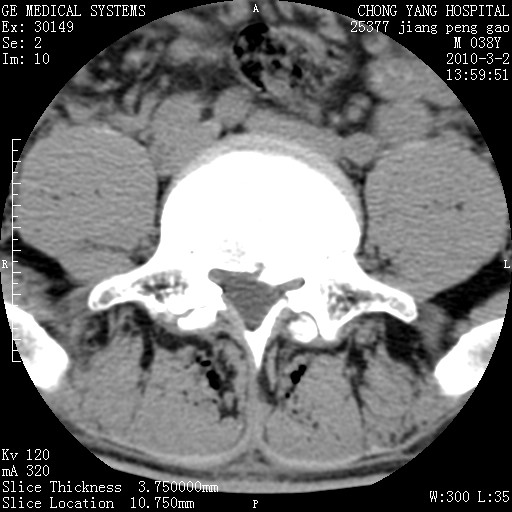

标题: CT24887:M38Y 反复腰痛 无外伤史 未做针灸 竖脊肌为何积气 [打印本页]

标题: CT24887:M38Y 反复腰痛 无外伤史 未做针灸 竖脊肌为何积气

软组织积气,考虑感染性病变。

退变,轻度增生/间盘膨出、l5椎后缘软骨结节。

肌间隙积气过多也为退变表现。

椎间盘突出,软组织积气。